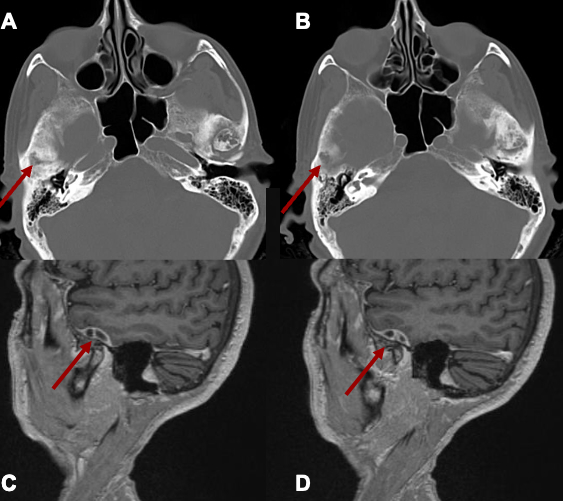

A 67-year old woman with chronic hypertension, hyperlipidemia and diabetes mellitus non-compliant to medication presented with a 10-day history of recurrent visual phenomena in the left visual field. She described stationery multi-coloured flashing lights which decreased in intensity, brightness and size after 3 minutes. She was alert and conscious during attacks. There was no limb jerking. Neurological examination was normal with no visual field defect. Capillary glucose was 28.1 mmol/L, Hba1c 9% and B-hydroxybutyrate < 0.1. She was treated with actrapid 8 units, glipizide 5 mg BD and empagliflozin 12.5 mg OM. Interictal electroencephalogram was normal with no epileptiform activity. Brain magnetic resonance imaging revealed restricted diffusion in the right occipital cortex with corresponding cortical thickening and increased FLAIR signal with subtle hypodensity on GRE sequence. Her visual symptoms improved dramatically with hydration and diabetic control. She was treated with a short course of keppra. One month later repeat MRI brain showed resolution of the DWI and FLAIR abnormalities.

Conclusions:

Visual hallucinations are an uncommon but well recognised and fully reversible complication of HHS. Clinicians should not forget HHS in the workup of occipital lobe.

Initial dwi